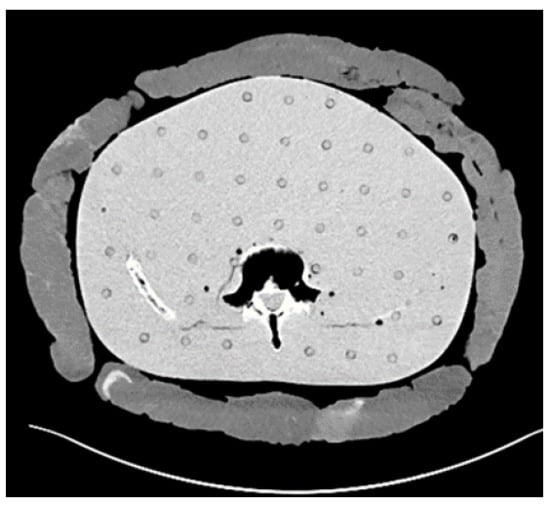

2.1. Phantom Preparation

2.2. Scanning Protocol